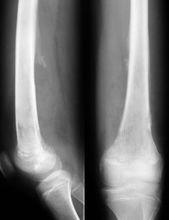

急性化膿性骨髓炎1、詳細檢查並詳閱X線片,明確死骨及死腔位置,確定手術切口

途徑等。